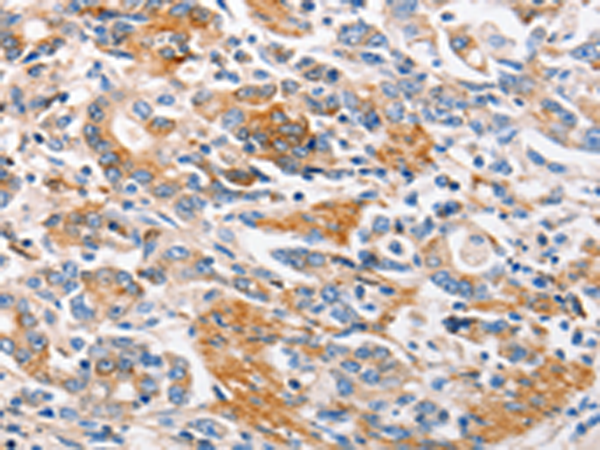

分类: 科研抗体货号: P11015别名: CMM5, MSH-R, SHEP2应用: IHC反应种属: Human, Mouse